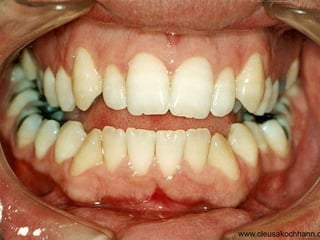

O documento apresenta registros odontológicos de um paciente ao longo de vários anos, incluindo panorâmicas iniciais e subsequentes, remodelações de arcadas dentárias superiores e inferiores ao longo de 7 meses, vedamentos labiais e registros de máxima intercuspidação e guias caninas nas datas listadas.